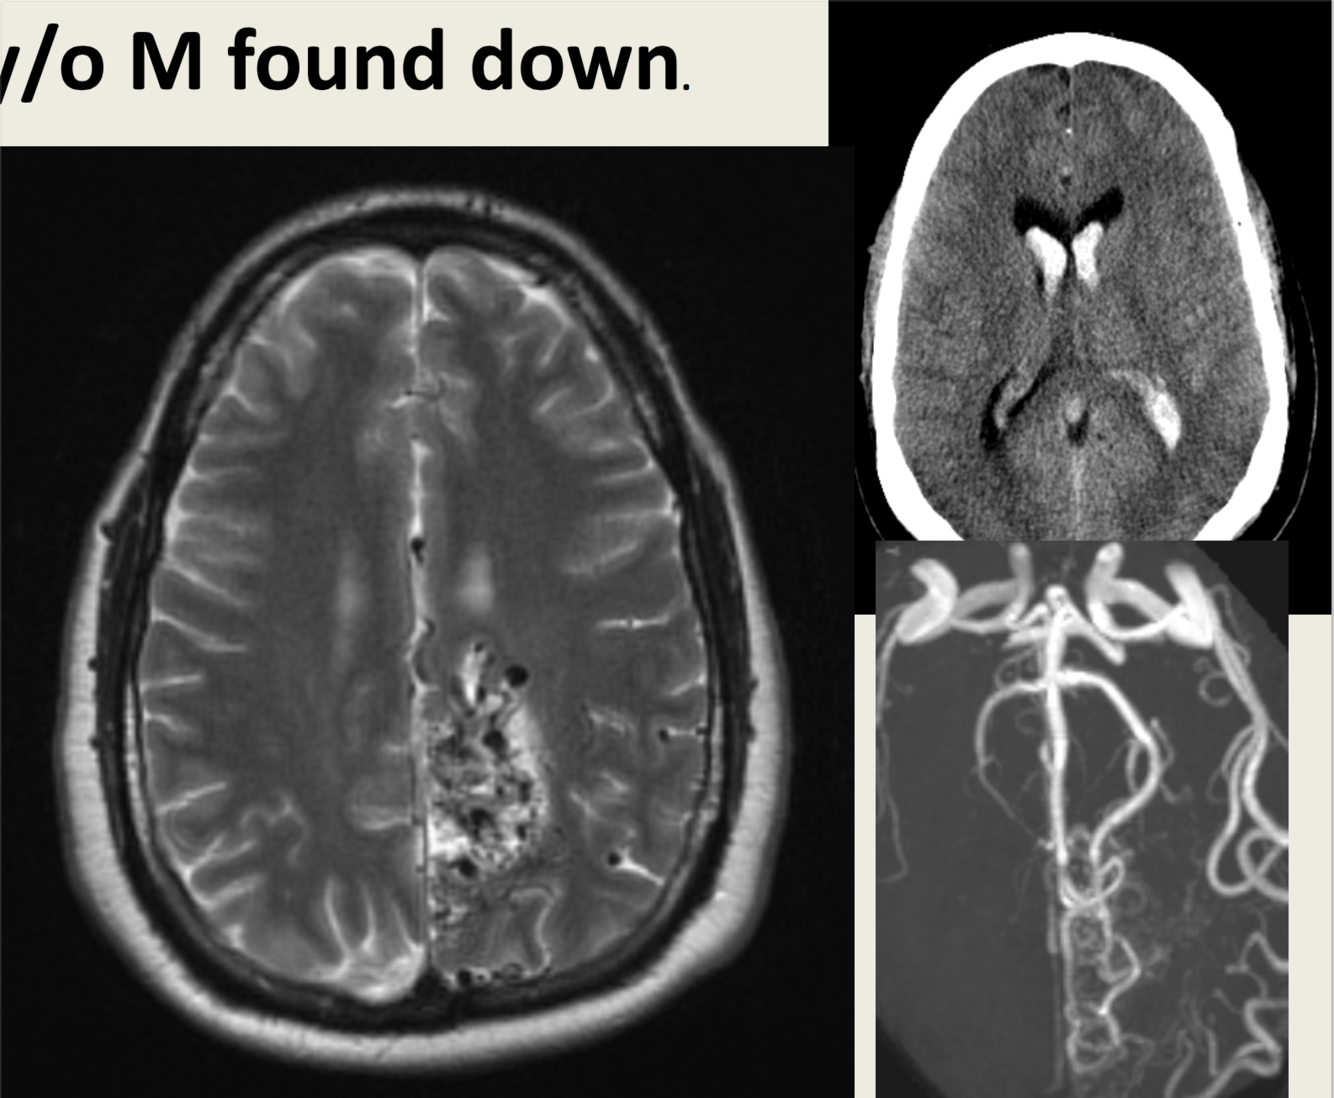

39 y/o M found down.

Intraventricular bleed due to AVM